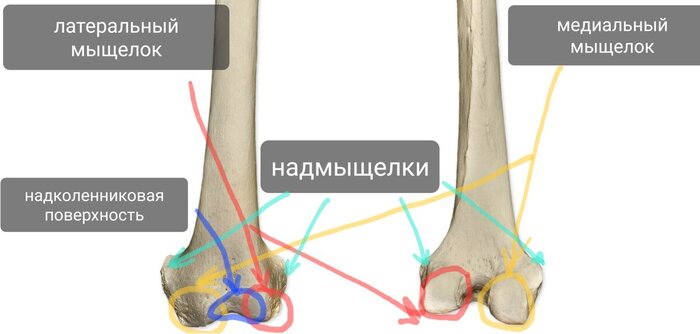

Проксимальный эпифиз сформирован медиальным и латеральным мыщелками, на которых расположены суставные поверхности, образующие большеберцовую часть коленного сустава. Между суставными поверхностями есть костные площадки - переднее и заднее межмыщелковые поля, к которым крепятся передняя и задняя крестообразные связки соответственно (внутренние связки коленного сустава).

В области медиального мыщелка находится точка крепления полуперепончатой мышцы.

Сбоку латерального мыщелка находится суставная поверхность проксимального (верхнего) межберцового сочленения (сустав с малоберцовой костью).